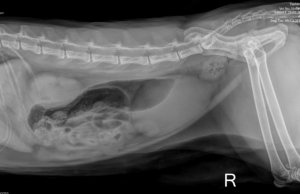

07.12.2021 Bin mit Emily in der TK Beitrag #79 G Gast52809 Gast Röntgenbilder im Normalzustand bis auf den Dickdarm der war noch etwas aufgegast.